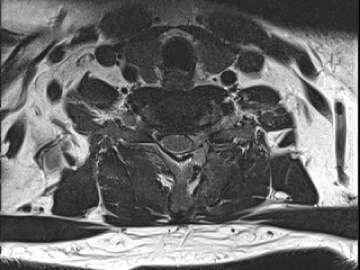

목디스크 수술 치료

2019.05.25

2022.09.13

2022.11.10

2022.11.16